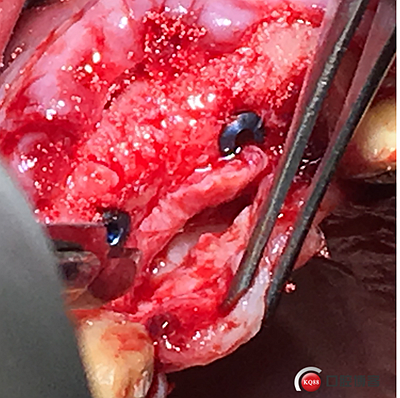

大家注意這個動作,雖然不翻瓣,但要將唇側(cè)倒凹處骨膜剝離。

將骨粉塞入剝離的骨膜下間隙里既唇側(cè)倒凹處,盡量塞滿。